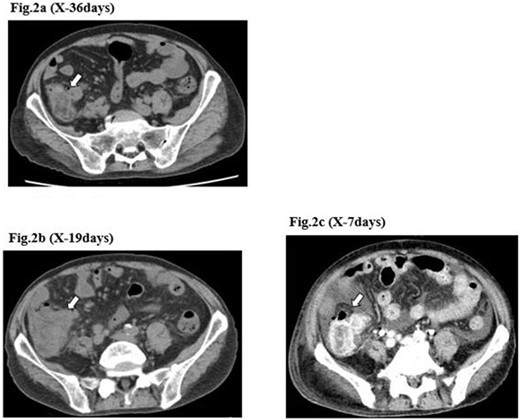

A 71-year-old man was diagnosed with advanced non-small cell lung carcinoma and pleura and lymph node metastasis. He received carboplatin, paclitaxel, bevacizumab and atezolizumab every 3 weeks as first-line chemotherapy for 4 months. As the pleural dissemination worsened, docetaxel and ramucirumab were administered as second-line treatment. The patient had three episodes of ileocecal diverticulitis following chemotherapy, all of which were treated conservatively with antimicrobials and fasting therapy. The diverticulitis episodes and computed tomography (CT) images are shown in Figs 1 and 2a–c. During the fourth diverticulitis episode, the patient presented with fever and abdominal pain, worsening after 5 days. Physical examination revealed tenderness and rigidity throughout the abdomen. Vital signs were stable, but body temperature was 37.7°C. Laboratory data showed inflammation with a white blood cell (WBC) count of 21 400/μL and a C-reactive protein (CRP) level of 23.8 mg/dL. Abdominal CT imaging showed ascites and intra-abdominal free air around the right-side colon (Fig. 3). Hence, we suspected a right-side colon perforation with acute diffuse peritonitis and performed an emergency laparotomy with a midline incision. Surveying the small bowel revealed that ileal perforation occurred only a few centimeters proximal to the ileocolic valve (Fig. 4). The patient underwent ileocecal resection, ileostomy and a colonic mucous fistula.

CT image of the ileocecal diverticulitis. The image shows that ileocecal diverticulitis (arrows) has occurred three times (a–c) until the diverticular perforation.